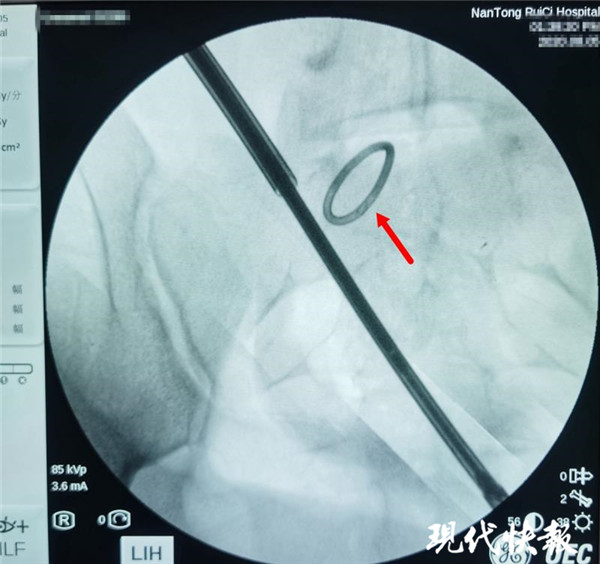

△術(shù)中X光,可清晰看到節(jié)育環(huán)

通過(guò)反復(fù)的X光定位,醫(yī)生終于發(fā)現(xiàn)了節(jié)育環(huán)的蹤跡,這枚“O”型節(jié)育環(huán)已經(jīng)跑到了乙狀結(jié)腸中段右側(cè)系膜內(nèi),并且穿透了乙狀結(jié)腸右側(cè)壁肌層,貫穿腸腔。醫(yī)生分離切開(kāi)腸系膜后,看見(jiàn)有近一半的節(jié)育環(huán)嵌頓在腸腔內(nèi)。之后胡偉和吳忠新相互配合,將節(jié)育環(huán)完整取出,并根據(jù)術(shù)中談話(huà)時(shí)患者家屬選擇的手術(shù)方案,對(duì)腸壁的兩處瘺孔進(jìn)行了修補(bǔ)縫合,手術(shù)順利結(jié)束。